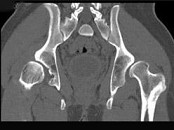

- 单项选择题男,23岁, 跛行,外展受限, 两下肢不等长,结合图像, 最可能的诊断是 ( )

A、髋关节中心脱位

B、髋关节后脱位

C、髋关节前脱位

D、先天性髋内翻

E、髋关节结核